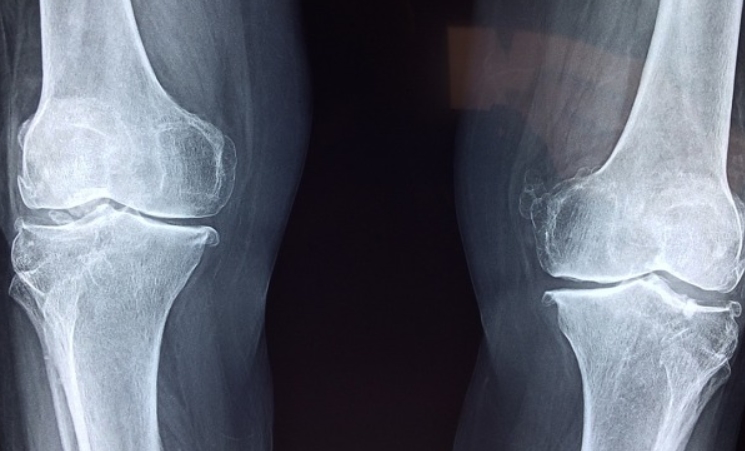

무릎 관절염 초기증상

무릎 관절염은 퇴행성 관절염이 가장 흔합니다. 나이가 들면서 연골이 닳고, 무릎이 붓거나 아픈 증상이 나타납니다.

- 계단을 오르내릴 때 무릎이 아프고 힘이 빠짐

- 장시간 앉아 있다가 일어날 때 무릎이 뻣뻣함

- 무릎에서 '뚝뚝' 소리가 나거나, 부종이 생김

- 심한 경우 무릎 모양이 O자로 변형됨

저희 부모님도 무릎이 아파서 병원을 찾았는데, 초기에 관리하면 연골 손상을 늦출 수 있다고 하시더라고요. 약물치료와 운동을 병행하면 효과가 좋다고 하니 꾸준한 관리가 필요합니다.